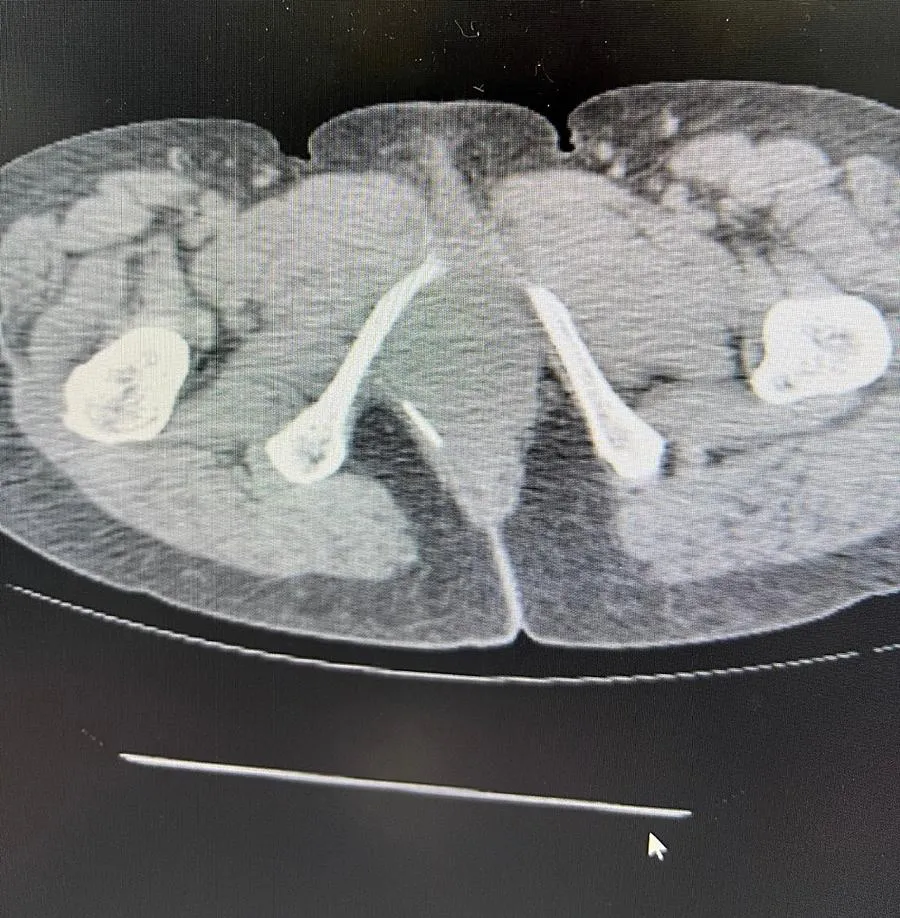

Ảnh chụp cắt lớp vi tính và đoạn tăm tre dài. |

Đến lần thứ ba do cơn đau ngày càng khó chịu nên bệnh nhân đến Bệnh viện Đa khoa Bình Thuận khám. Tại đây, các bác sĩ khoa Ngoại tổng quát tiến hành siêu âm thì phát hiện khối áp xe, nghi ngờ có dị vật nên cho chụp cắt lớp vi tính (CT).

Sau khi chụp CT, các bác sĩ phát hiện đoạn tăm tre dài và đầu nhọn đã đâm thủng trực tràng nằm trong cơ thắt gây ra ổ áp xe nên tiến hành phẫu thuật đưa dị vật ra ngoài an toàn.